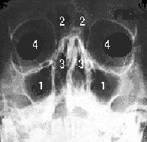

1) Seni mascellari 2) Seni frontali 3) Seni etmoidali 4) Orbite